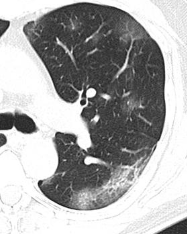

Patrón reticular / intersticial IMAGEN rx

Líneas de Kerley